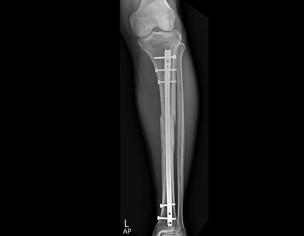

aoa please dr tell me when it will b healed . 5 march 2023 opreation . now october how many time to take to heel completly . age patient 47 years. patient got accident in january both legs are damag right leg is most damage and then in feb right leg amputed above knee . this is left leg x ray . want to ask how many time to take heeling completly. please tell me in how many time to take complete heeling

Xrays show good healing. Is the patient walking? Ask the patient to walk stick or crutch on right side. The more the patient walks on this left leg, the better remodeling there wiil be. In short, patient can walk on left leg

your injury is a severe and operation done very well you start to weight beering on th injured leg wait 18 to 24 months for full recovery